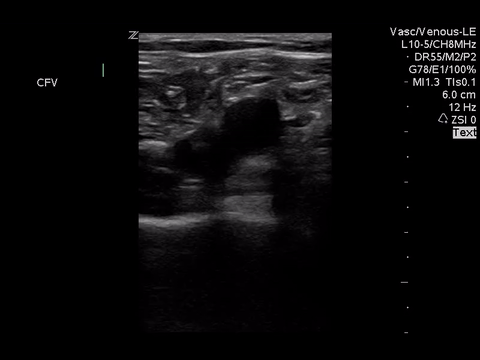

Right lower extremity

In each of these images it appears the vein fully collapses with compression. We can conclude that there is likely no DVT present within the limitations of the 2-point compression scan (see discussion for further details)